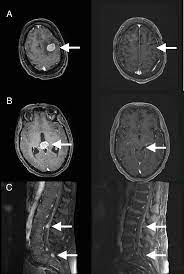

Diplopia As The Initial Symptom Of Multiple Myeloma In A Patient With Sarcoidosis Bmj Case Reports

Diplopia As The Initial Symptom Of Multiple Myeloma In A Patient With Sarcoidosis Bmj Case Reports from casereports.bmj.com